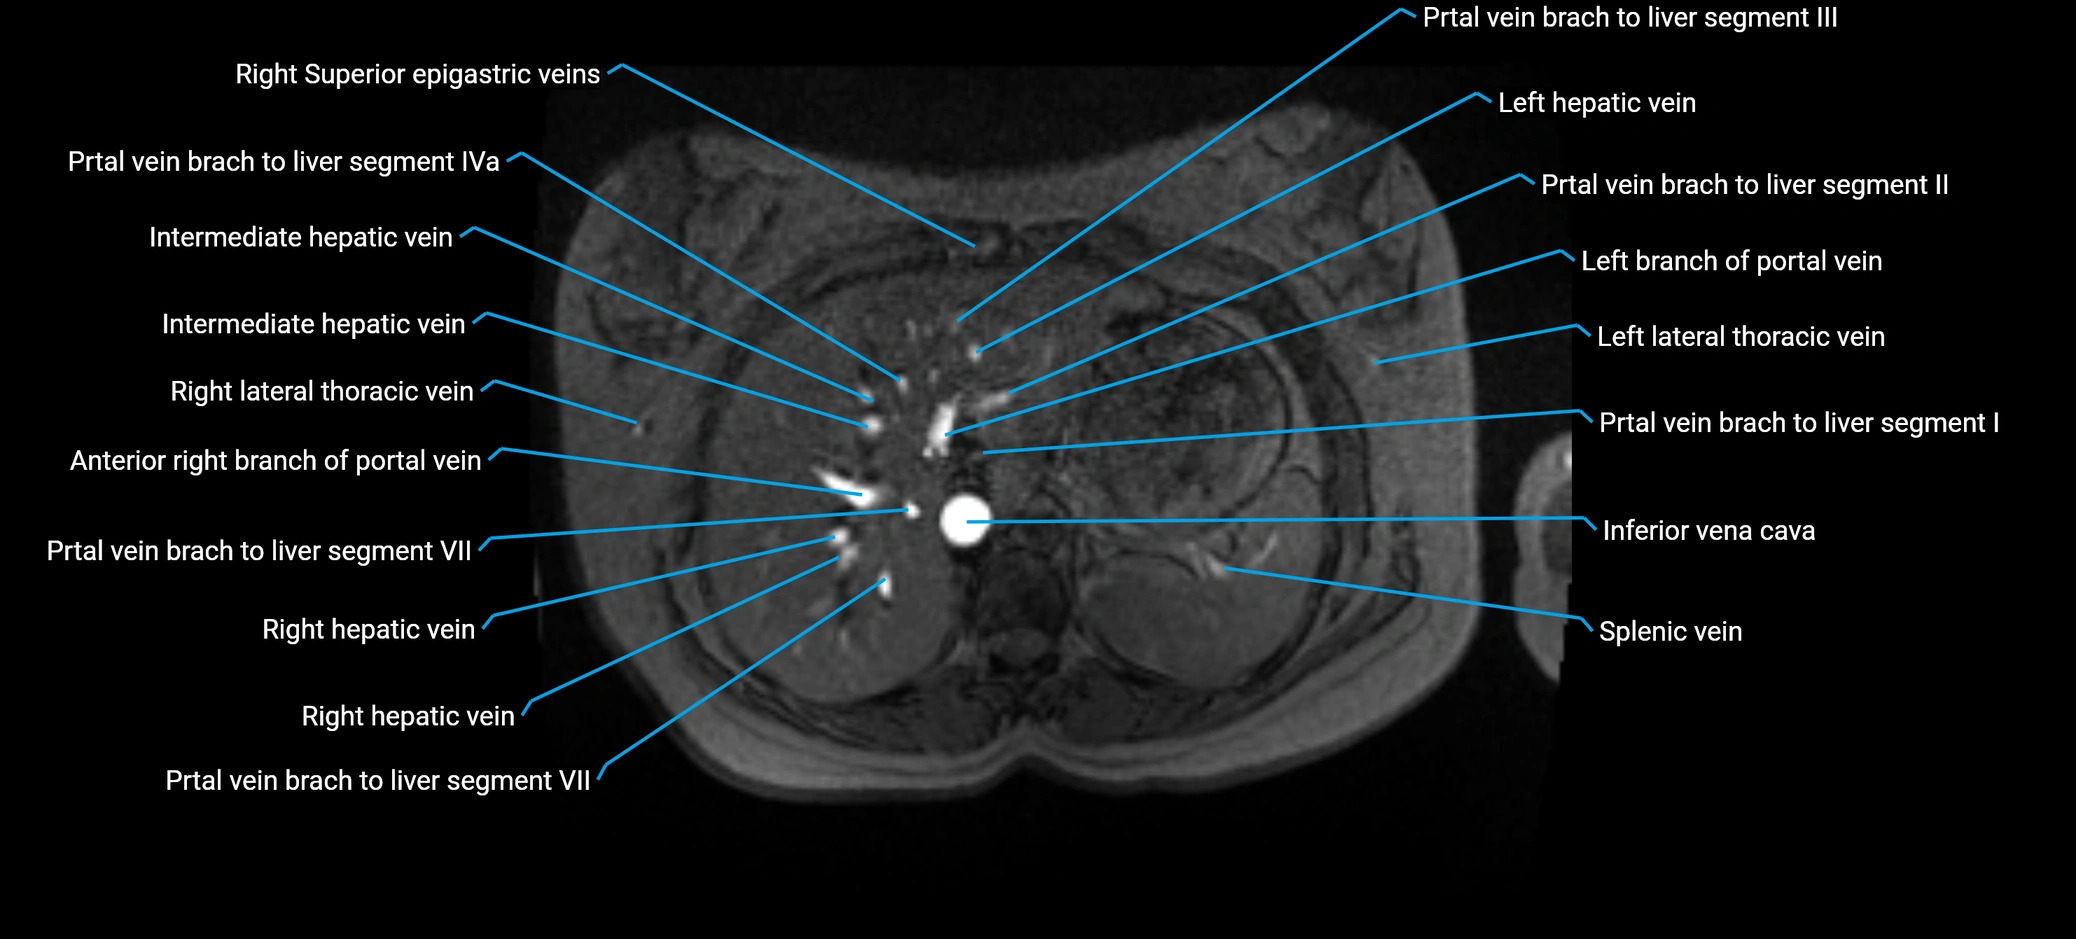

The anterior right branch of the portal vein is a major intrahepatic division of the right portal vein. After the main portal vein bifurcates into right and left branches, the right portal vein divides into anterior and posterior segmental branches.

The anterior right branch supplies the anterolateral liver segments (Segment V) and anteromedial liver segments (Segment VIII) within the right hepatic lobe. It operates as a key vascular route delivering nutrient-rich portal venous blood to the central and superior right liver.

This segmental vasculature is of major importance in hepatic surgery, embolization, segmental resection, transplantation, and imaging-based liver segmentation.

MRV TOF (Time-of-Flight MR Venography):

• Appears as a bright, high-signal vascular channel representing flowing blood

• Clearly shows branching pattern of right portal vein into anterior and posterior branches

• Best in coronal or axial reconstructions for segmental mapping

• No need for contrast, relies on flow-related enhancement